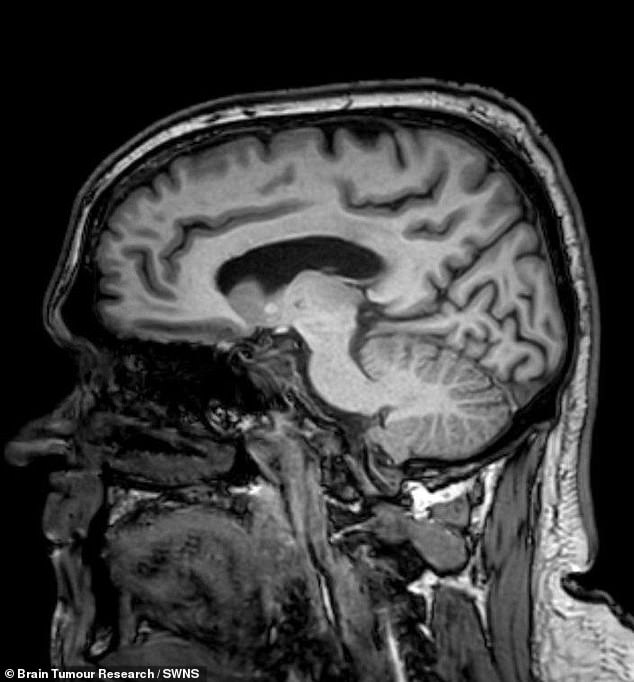

In 2022, Mr. Brunt suffered a sudden seizure while driving, causing him to crash his van and sustain severe injuries, including a bitten tongue and blood loss. Emergency responders noted the crash occurred without signs of intoxication, prompting his ex-partner to urge immediate hospitalization. At Chesterfield Royal Hospital, a CT scan revealed a glioblastoma, an aggressive, incurable form of brain cancer. The discovery came as a shock, as initial expectations were for trauma-related bleeding from the crash, not a malignant tumor.

Mr. Brunt was referred to Royal Hallamshire Hospital in Sheffield, where surgeons identified a brain mass requiring urgent removal. He underwent a craniotomy, a procedure that left him temporarily unable to walk or speak. Initially, doctors estimated his survival at seven months. However, a combination of radiotherapy and chemotherapy extended his life. In October and November 2023, he completed 30 sessions of radiotherapy, followed by six cycles of chemotherapy in 2024. Though he experienced fatigue and hair loss, he tolerated the treatments well.